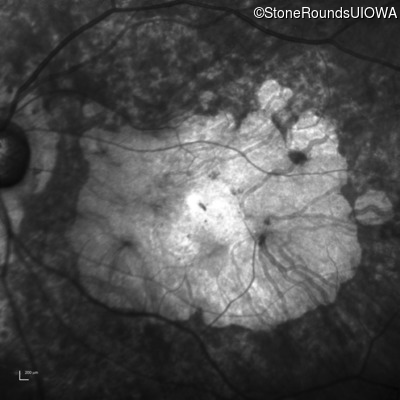

Infrared Fundus Photograph - Right - 10/200 -2 sc

Exemplar